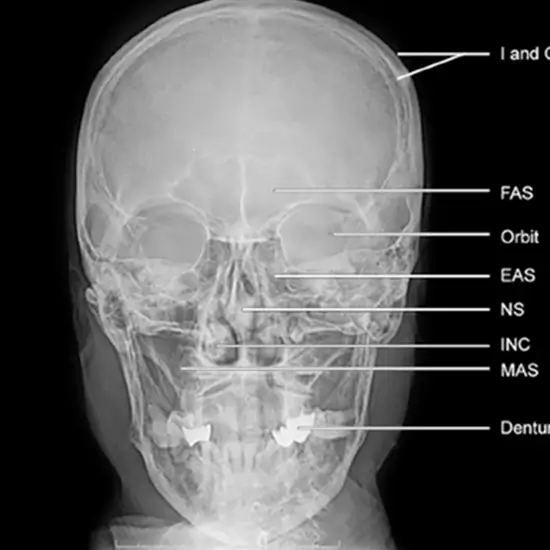

To get a clear orbits (postero-anterior) image of the skull and demonstrate pathology such as skull fractures (orbits) with medial and lateral displacement. Mandible fractures are seen in postero-anterior view. In pediatrics, this perspective is utilized to reduce the equivalent dose to the eye's lens.

This view is useful in assessing:

• Orbits

• Internal auditory meatus

• Skull fracture

• Paget disease

• Neoplastic change

• Frontal bone

• Ethmoid and frontal sinus

• Structure seen in dental region

• Mastoid sinus

• The sphenoid has larger and smaller wings.